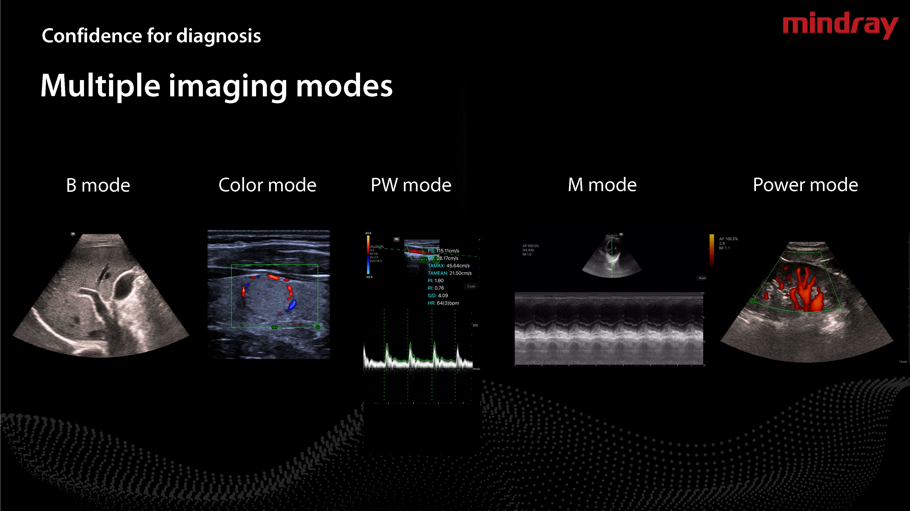

- Applicazione intuitiva,misure Doppler in tempo reale.

- Sonde a frequenza variabile,Color Doppler,Pulsed Wave,Power Doppler.

- Armonica di tessuto,Spacial Compound ,Connessione WiFi e USB ,velocità wireless elevato.